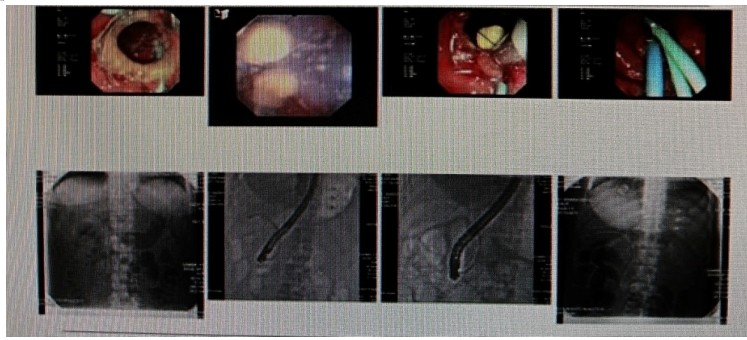

消化內(nèi)科肝病亞??茍F(tuán)隊(duì)詳細(xì)討論,分析患者情況后,取消了周女士的肝穿刺活檢檢查,建議患者先行超聲胃鏡下膽胰掃查。在內(nèi)鏡醫(yī)師第三只眼——超聲胃鏡的掃查下,發(fā)現(xiàn)引起周女士肝功能受損的罪魁禍?zhǔn)?/span>原來(lái)是膽總管末端結(jié)石!伍友興主任醫(yī)師帶領(lǐng)團(tuán)隊(duì)給予患者行ERCP下取石后,周女士未再出現(xiàn)腹痛,肝功能恢復(fù)正常。

無(wú)獨(dú)有偶,劉先生也為反復(fù)出現(xiàn)肝功能受損到多家醫(yī)院就診檢查,未能找到原因,來(lái)到衡陽(yáng)市中心醫(yī)院消化內(nèi)科就診,希望能在肝穿刺活檢下得出病因。在行肝穿刺活檢之前,醫(yī)生建議劉先生行超聲胃鏡膽胰掃查,發(fā)現(xiàn)引起劉先生反復(fù)肝功能受損原因,亦是膽總管結(jié)石引起,在ERCP術(shù)取石術(shù)后,患者肝功能恢復(fù)正常,未再出現(xiàn)異常情況。

張丹霞主任醫(yī)師介紹,超聲內(nèi)鏡通過(guò)胃十二指腸自然腔道,可以將探頭貼近相應(yīng)的位置,近距離的觀察胰腺及膽道系統(tǒng),準(zhǔn)確捕捉到直徑小于5毫米的胰腺異常病灶及膽道系統(tǒng)病灶。而體表B超常受皮膚、脂肪或腸道氣體干擾。CT或磁共振檢查只能提供靜態(tài)圖像,且對(duì)膽胰管陰性結(jié)石或是未引起明顯膽管梗阻性的結(jié)石檢查有局限性,因此對(duì)于有輕微腹痛合并肝功能受損的患者,建議常規(guī)行超聲胃鏡下膽胰掃查。超聲胃鏡、腹部彩超、腹部CT、腹部MRI同為診斷膽管細(xì)微病變的四架馬車,在膽總管結(jié)石診斷方面,超聲胃鏡膽胰掃查同ERCP一樣,是敏感性高、特異性強(qiáng)的診斷方法。超聲胃鏡發(fā)現(xiàn)可疑病變,可以完成穿刺活檢,還可行囊腫穿刺引流、膽管減壓、消融術(shù)等。